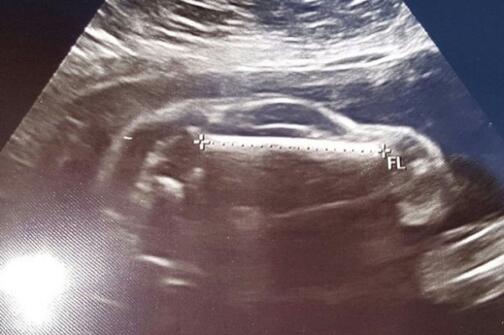

Một cặp vợ chồng đã vô cùng ngạc nhiên khi nhìn thấy trong ảnh siêu âm thai nhi không phải là một em bé mà là một chiếc ô tô thể thao.

Mới đây, một người dùng Reddit đã đăng tải hình ảnh siêu âm của vợ mình lên trang mạng trực tuyến này với dòng chia sẻ: “Vợ tôi mang thai một ‘chiếc xe ô tô thể thao’“.

Hầu hết mọi người đều đồng ý rằng cậu bé chưa chào đời của vợ chồng anh chàng này có hình dạng giống hệt một chiếc xe ô tô. Nhiều người đã tỏ ra vô cùng thích thú với bức ảnh siêu âm của hai vợ chồng.